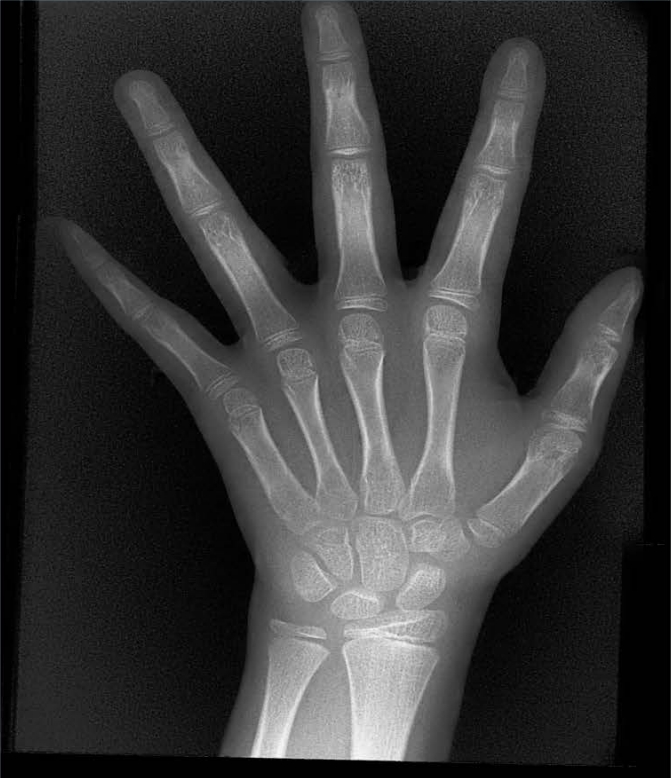

X射線骨齡儀通過拍攝兒童手腕部(指骨、掌骨、腕骨)的X射線影像,依據(jù)骨骼的形態(tài)、大小、鈣化程度等特征,結(jié)合評(píng)估標(biāo)準(zhǔn)(如《中國(guó)青少年兒童手腕骨成熟度及評(píng)價(jià)方法》,簡(jiǎn)稱《中華-05》標(biāo)準(zhǔn))進(jìn)行骨齡判定。相較于傳統(tǒng)檢測(cè)方式,X射線骨齡儀具有輻射劑量低、影像清晰度高、檢測(cè)效率高的優(yōu)勢(shì),能精準(zhǔn)捕捉骨骼發(fā)育的細(xì)微變化,為骨齡評(píng)估的準(zhǔn)確性提供保障。